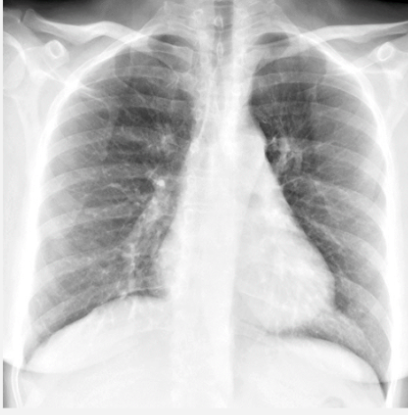

Chest xray blue bloater

A

INCREASED interstitial markings *

sx:

- Chest is noisy with rhonchi, wheezes

How well did you know this?

Chest radiograph:

-Increased interstitial markings (“dirty lungs”)

-Diaphragms not flattened